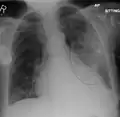

| A chest X-ray showing a very prominent wedge-shape bacterial pneumonia in the right lung | |